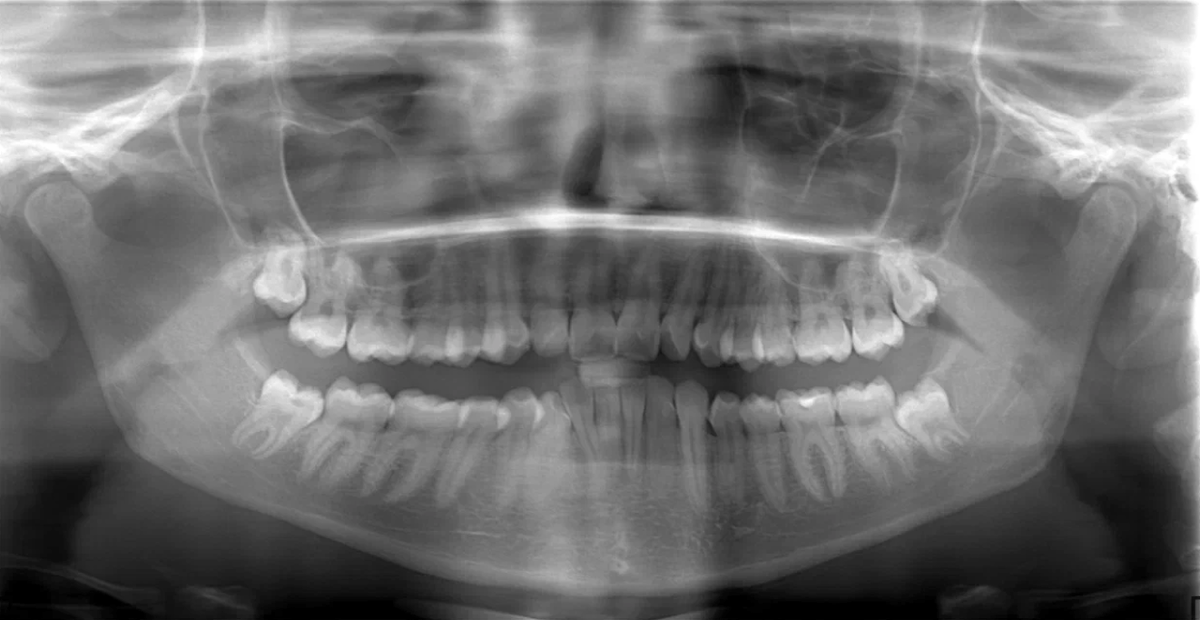

Как проходит удаление?

Процедура проводится под местной анестезией — боль вы не чувствуете. Весь процесс занимает от 15 до 45 минут, в зависимости от сложности.Процедура всегда начинается с диагностики: в клинике Probel перед удалением обязательно делают панорамный снимок. Он помогает хирургу оценить расположение корней, близость к нервам и выбрать наименее травматичную тактику.